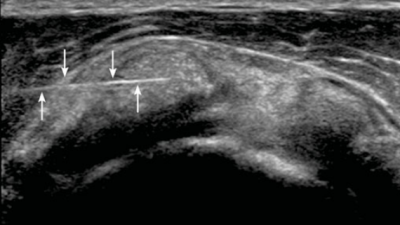

Wat zien we op een echo bij kalk in de schouder?

Een kalkafzetting is op echo direct zichtbaar. Het is een van de diagnoses die we het snelst kunnen stellen.

Kalk verschijnt op de echo als een heldere witte vlek in de pees, vaak met een donkere schaduw erachter. Die schaduw vertelt ons iets belangrijks: hoe sterker de schaduw, hoe harder de kalk.

Echografisch beeld van een kalkafzetting in de schouderpees: witte heldere vlek met donkere schaduw, kenmerkend voor harde kalk bij tendinitis calcarea

Hard of zacht kalk

Dit onderscheid is cruciaal voor de behandeling:

• Harde kalk (sterke schaduw, scherpe randen): de kalk zit in de rustfase. Stevig ingekapseld in de pees. Een barbotage is lastiger maar mogelijk.

• Zachte kalk (vage of geen schaduw, wolkige randen): de kalk is in de oplossingsfase. Het lichaam is bezig met opruimen. Dit is vaak het pijnlijkste moment, maar de kalk is goed weg te spoelen met een barbotage.